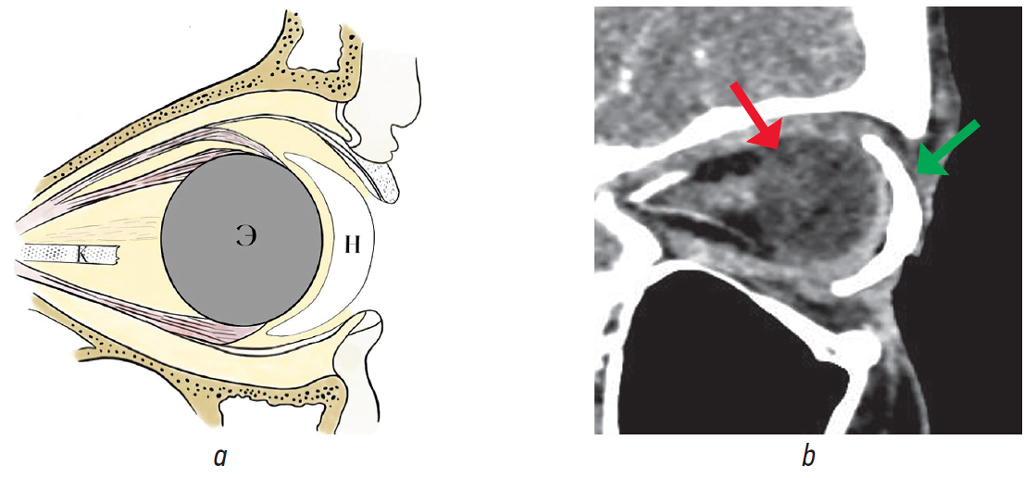

Fig. 21. Eyeball endoprosthetics: a — schematic representation of orbital structures (Э — endoprosthesis, K — nerve stump, Н — external cosmetic prosthesis); b — MSCT of the orbit, sagittal reconstruction, soft tissue window mode, with intravenous contrast, state after endoprosthetics of the left globe. In the anterior part of the left orbit, a centrally located endoprosthesis is visualized (red arrow), round in shape, with homogeneous structure, of 20 mm in diameter, average density of –33 HU, no additional inclusions in the area of the prosthesis were identified, in the anterior part an endoprosthesis capsule with clear, even contours is visualized. An external cosmetic prosthesis (green arrow) is adjacent to the front surface of the endoprosthesis, with the presence of air vacuoles between them

Рис. 21. Эндопротезирование глазного яблока: a — схематическое изображение структур орбиты (Э — эндопротез, К — культя нерва, Н — наружный косметический протез; b — МСКТ орбит, сагиттальный срез, режим мягкотканного окна, с внутривенным контрастированием, состояние после эндопротезирования левого глазного яблока. В переднем отделе левой орбиты визуализируется центрально расположенный эндопротез (красная стрелка), округлой формы, однородной структуры, диаметром 20 мм, средней плотностью –33 HU, дополнительных включений в области протеза не выявлено, в передней части визуализируется капсула эндопротеза с чёткими ровными контурами. К передней поверхности эндопротеза (к опорной культе) прилежит наружный косметический протез (зелёная стрелка), с наличием вакуолей воздуха между ними